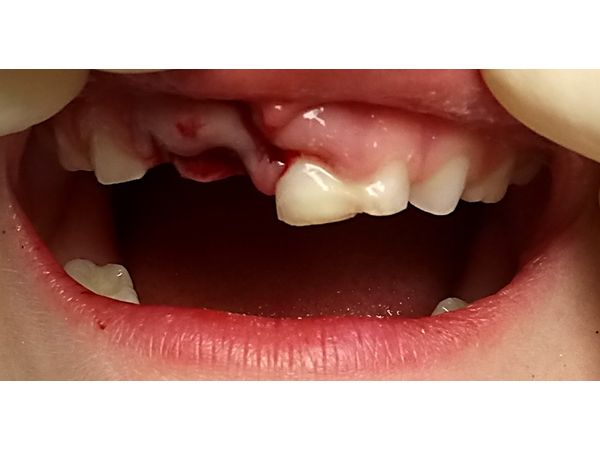

У ребёнка начали шататься верхние передние зубы. Два правых зуба выпали из лунки, прикрепились к десне и при смыкании упирались в нижние зубы, вызывая сильную боль, поэтому девочка не могла закрыть рот. Пациентка также не могла проглатывать слюну, принимать пищу и пить.

При осмотре лицо симметричное. Кожа нормального цвета. На подбородке остались царапины. Верхняя губа отекла, прощупывание вызывало боль. Рот могла открыть полностью, но закрыть не получалось из-за смыкания правых резцов снизу и сверху. Верхние правые резцы (зубы 51 и 52) располагались вне лунок, были прикреплены к десне. Подвижность III степени (шатались во все стороны). Лунки заполнены сгустками крови. Левый верхний центральный резец (зуб 61) двигался влево-вправо и вперёд-назад. Простукивание резко болезненное.

Перелом корня зуба 61, полный вывих (экзартикуляция) зубов 51 и 52.